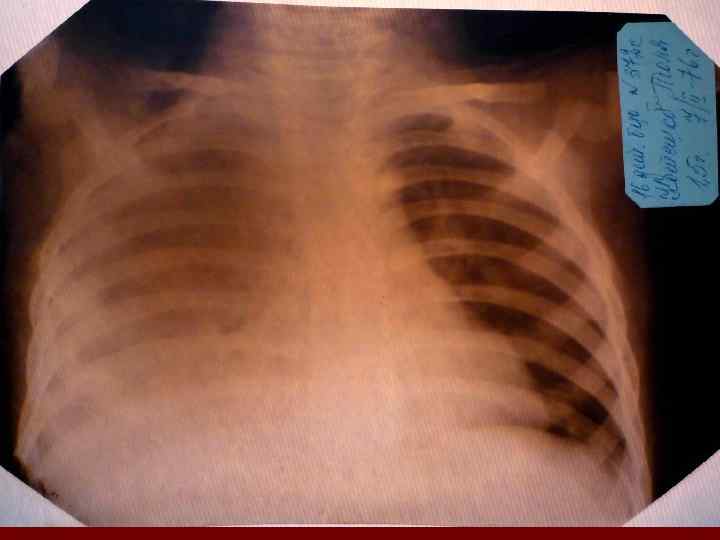

Долевая пневмония характеризуется лобарным пневмоническим инфильтратом. Крупозная ( пневмококковая) пневмония диагностируется прежде всего по клиническим данным. Крупозная пневмония сохраняет свою типичную картину пневмококковой пневмонии: острое начало с характерными клиническими данными, циклическое течение, несклонность к деструкции, гомогенной и лобарной инфильтративной тенью при рентгенологическом исследовании. Вместе с тем, широкое использование антибиотиков способствовало значительному снижению числа крупозных пневмоний у детей. Интерстициальная – редкая форма пневмоний, при которой оказывается поражен прежде всего интерстиций. Как правило, интерстициальная пневмония обусловлена вирусами, пневмоцистами, внутриклеточными микроорганизмами и грибами.

Морфологическую форму пневмонии определяют по клинико – рентгенологическим данным: выделяют очаговую, очагово – сливную, долевую ( крупозную), сегментарную и интерстициальную пневмонии. Очаговая – наиболее распространенная форма. Пневмонические очаги чаще бывают размером 1 см и более. Очагово – сливная – инфильтративные изменения в нескольких сегментах или во всей доле легкого, на фоне которых могут быть видны более плотные участки инфильтрации и/или полости деструкции. Сегментарная – в процесс вовлекается весь сегмент, который, как правило, находится в состоянии гиповентиляции, ателектаза. Морфологическая картина воспаления при очаговых и сегментарных пневмониях связана с первичным инфекционным воспалением в бронхах, что дает основание отнести эти варианты поражения легочной ткани к бронхопневмониям, нередко сопровождающихся бронхообструктивным или бронхообтурационным синдромами. В настоящее время данный тип пневмоний у детей встречается наиболее часто.